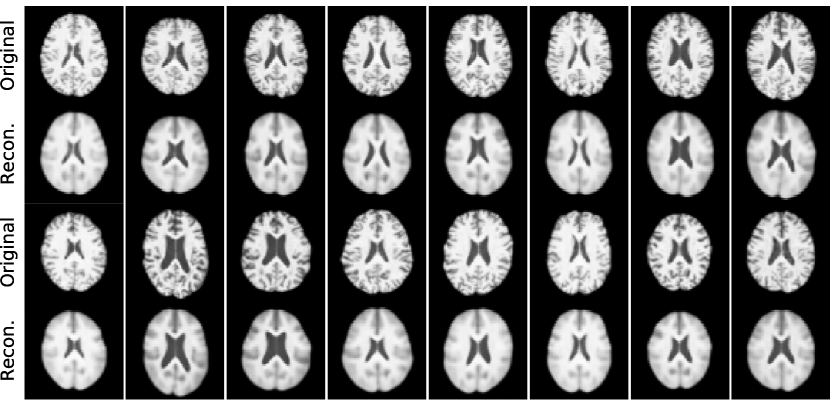

The learned DSCM is capable of all three levels of the causal hierarchy. We present the analysis of lower levels in Section B.3.1 and focus here on counterfactuals, shown in Fig. 5(b) (more examples in Section B.3.2). The difference maps show plausible counterfactual changes: increasing age causes slightly larger ventricles while decreasing the overall brain volume (first column). In contrast, directly changing brain volume has an opposite effect on the ventricles compared to changing age (second column). Intervening on ventricle volume has a much more localised effect (third column), while intervening on the categorical variable of biological sex has smaller yet more diffuse effects. Note how the anatomical ‘identity’ (such as the cortical folding) is well preserved after each intervention.

B.3 Additional Results

Likewise, we present more detailed analyses of the model trained on UK Biobank brain images and covariates, in terms of modelling the observational distribution and computing various counterfactual queries. (Continued on the next page.)

B.3.2 Counterfactual